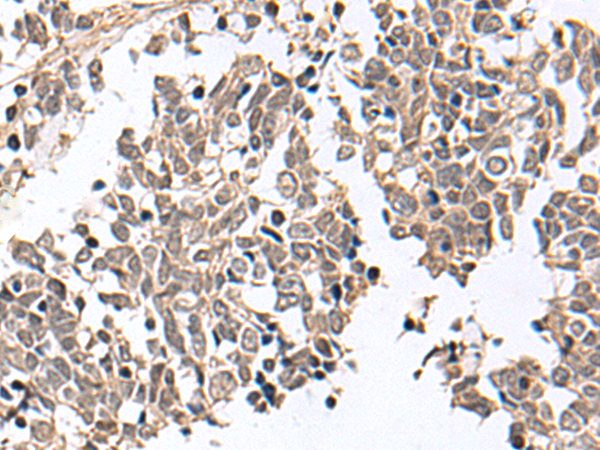

IHC positive control: |

Human cervical cancer and Human lung cancer |

IHC Recommend dilution: |

25-100 |